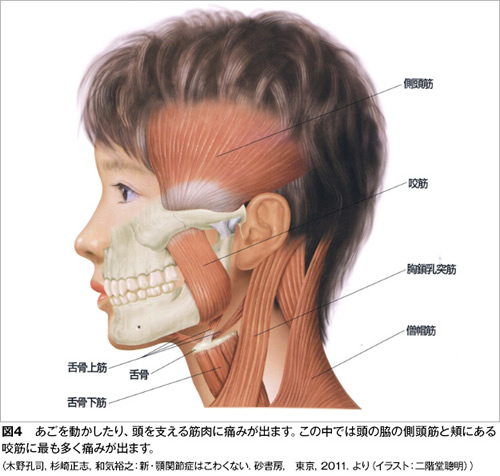

この2つの状態で来院される方が全体の60%ほどになります。

これ以外では顎関節そのものには痛みがないのですが、下顎を動かす筋肉がうまく働かなくなり、口を開けようとすると頬やこめかみの筋肉が痛むという状態(図4)、あるいは関節円板のずれはないのですが、口を開けようとすると顎関節が痛む捻挫に似た状態があります。